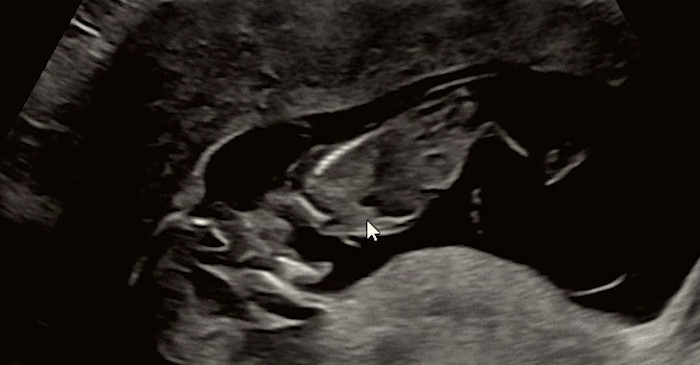

강은비는 영상을 통해 지난 3일 태아를 떠나보냈다고 밝혔다. 그는 임신 경과 중 정기 검진에서 모든 수치가 정상이라는 설명을 들었지만, 이후 양수가 감소했다는 소견을 받았다고 설명했다. 검사 과정에서 양수 누출 가능성이 제기되면서 상급병원으로 이송됐으며, 입원 후 이틀 만에 양수 수치가 0이라는 진단을 받았다고 전했다.

의료진은 조기 양막 파열이 의심된다는 판단 아래 절대 안정을 권고했고, 강은비는 소변줄을 착용한 채 추가로 이틀간 입원 치료를 받았다.

조기양막파열은 출산 진통이 시작되기 전에 양막이 먼저 파열돼 양수가 흘러나오는 상태를 말한다. 일반적으로 양막은 태아를 외부 충격과 세균으로부터 보호하고, 체온과 환경을 일정하게 유지하는 역할을 한다. 이 양막이 예정된 시기보다 빨리 파열되면 감염 위험이 급격히 높아지고, 태아에게 필요한 양수가 줄어들면서 여러 합병증 가능성이 커진다.

특히 임신 37주 이전에 발생하는 경우를 ‘조기 조기양막파열’로 분류하는데, 이 시기에는 태아의 폐와 장기 성숙이 충분하지 않은 경우가 많아 의료진의 판단이 매우 중요해진다. 양수가 지속적으로 빠져나가면 태아의 폐 발달이 제한될 수 있고, 탯줄 압박이나 자궁 내 감염으로 이어질 위험도 있다.

안타깝게도 강은비의 양수는 다시 생성되지 않았고, 임신 중단 가능성에 대한 설명을 듣고 더 큰 상급병원으로 전원했다고 밝혔다.

강은비는 해당 병원에서 태아가 가로로 누운 상태로 태반에 밀착돼 있었으며, 폐 발달이 더 이상 어려운 상황이라는 설명을 들었다고 전했다. 의료진은 태아가 매우 제한된 공간에서 버티고 있는 상태라고 판단했다.